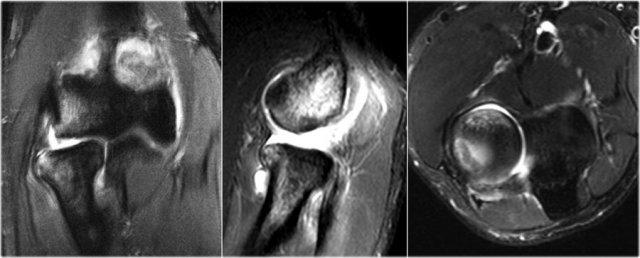

MR-arthrogram xác nhận tổn thương sụn xương.

Có gadolinium nằm giữa xương cánh tay và tổn thương sụn xương, cho thấy tổn thương này không ổn định.

Nếu không có gadolinium, hãy tìm dịch khớp chui xuống dưới mảnh sụn xương.

Có một mảnh thể tự do trong ngách sau của khớp quay-cánh tay.

Notice also the fragmentation as seen on the axial image.

Tổn thương sụn xương của chỏm con thường gặp ở vận động viên ném bóng và thể dục dụng cụ (11-15 tuổi), những người thường gặp nhiều vấn đề về cổ tay và khuỷu tay do chịu lực tỳ đè.

Here another case in a 20 year old gymnast.

Một lần nữa có hình ảnh thấu quang trên phim X-quang.

Hình ảnh MR-arthrogram cho thấy một số phù nề tủy xương trên mặt phẳng coronal.

Hình ảnh T1W mặt phẳng sagittal cho thấy bất thường xương dưới sụn, nhưng không có nhiều mảnh rời.

Có một số mỏng sụn, nhưng không có khuyết sụn.

Đây rõ ràng là một mảnh ổn định và không có dị vật khớp.